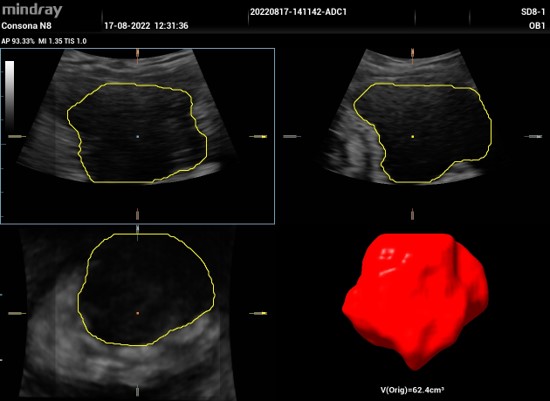

Smart Bladder : Automatické presné vypočítanie objemu močového mechúra. Po priložení volumetrickej brušnej sondy na oblasť močového mechúra a stlačení príslušného tlačítka softvér dokáže sám vyhľadať močový mechúr, tento zobrazí a obkreslí v troch na seba kolmých rovinách. Následne vypočíta objem mechúra. Tento obraz je možné otáčať vo všetkých 3 rovinách.

3D mechúra